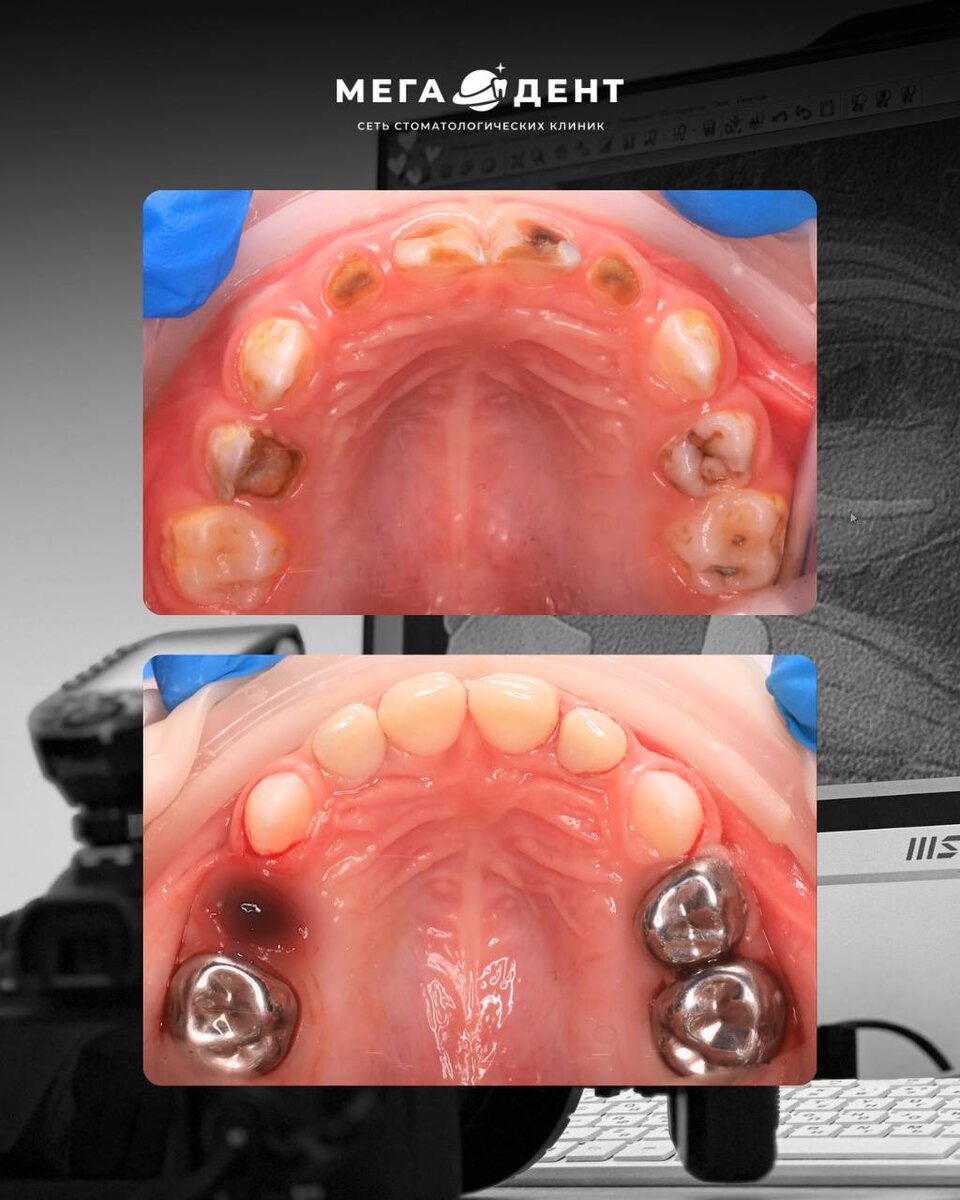

Комплексное лечение 15 зубов за 3,5 часа ⏰

К нам обратились родители маленького пациента 3х лет, с жалобами на множественные кариозные полости и боль при приёме пищи.

В подобных случаях нередко принимается радикальное решение - удаление разрушенных зубов, поскольку объём поражения был значительным, а ситуация выглядела критичной.

Наша задача состояла в другом - сделать всё возможное, чтобы сохранить молочные зубы до их естественной смены!

После тщательной диагностики и составления подробного плана лечения было принято решение о проведении комплексной санации под общим обезболиванием.

Это позволило выполнить весь объём работы за 1 визит: безопасно и контролируемо.

В ходе лечения проведено:

✔️профессиональная гигиена

✔️лечение 15 зубов (лечение кариеса, пульпитов и периодонтита)

✔️удаление 1 зуба (по строгим показаниям)

✔️восстановление зубов пломбами и циркониевыми коронками

Общее время работы команды - 3,5 часа ⏰

Благодаря слаженной работе специалистов удалось сохранить зубы, устранить очаги инфекции и вернуть полноценную функцию и эстетику ✔️